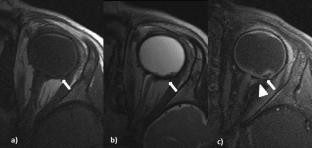

Fig. 1

High-resolution MRI using orbit surface coils for the evaluation of metastatic risk factors in 143 children with retinoblastoma

Part 1: MRI vs. histopathology

Sensitivity/specificity for the detection of metastatic risk factors using high-resolution MRI with orbit surface coils were 60 %/88.7 % for postlaminar optic nerve infiltration, 65.5 %/95.6 % for choroidal invasion, 100 %/99.3 % for scleral invasion, and 100 %/100 % for peribulbar fat invasion, respectively. The results increased for the detection of advanced metastatic risk factors, 81.8 %/89.1 % for deep postlaminar optic nerve infiltration, 70.6 %/97.6 % for massive choroidal invasion.